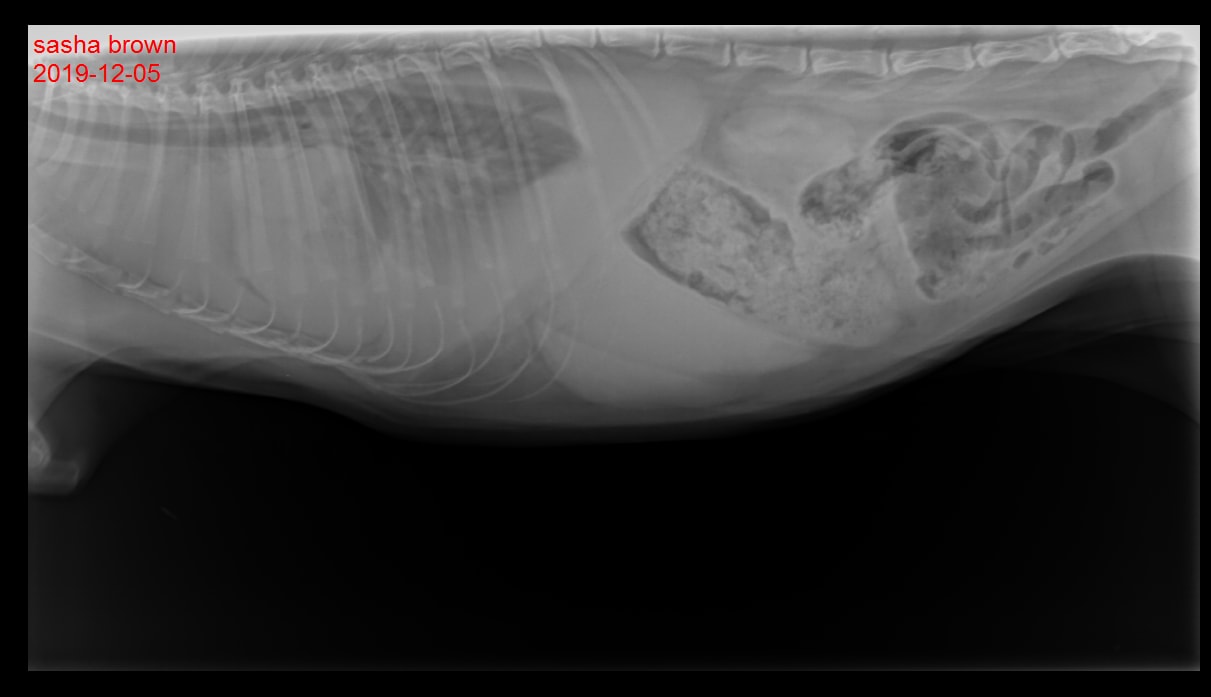

Pet's info: Cat | Himalayan | Female | spayed | 3 years and 4 months old | 12 lbs

My 3-year-old recently died to compound issues, but the worst was a massive chest tumor, that wasn't found until she was already in crisis. At the time I could not bear to ask the vet to point it out to me on the x-ray, but they did give me a copy to view later. I hoped it would be obvious to the untrained eye, but, I'm looking at it and guessing... I'd love an expert to help narrow what I'm seeing since I'm no expert at what I'm seeing.

First off, I'm so sorry Sasha died. Please accept my condolences for your loss. I wish I could be with you to explain this, but I will do my best. So her heart is completely obscured in this x-ray. You should be able to see the heart and both lungs in a normal x-ray. In this one, you can't see her heart or one of her lungs, that should be at the bottom of her chest. There is a big circular mass that the top right part of it touches the lung. I suspect that is the tumor. In addition, there are scattered white spots through the visible lung and in the chest. Those would be metastasis from the original tumor. Again, I'm so sorry and I hope this helps.